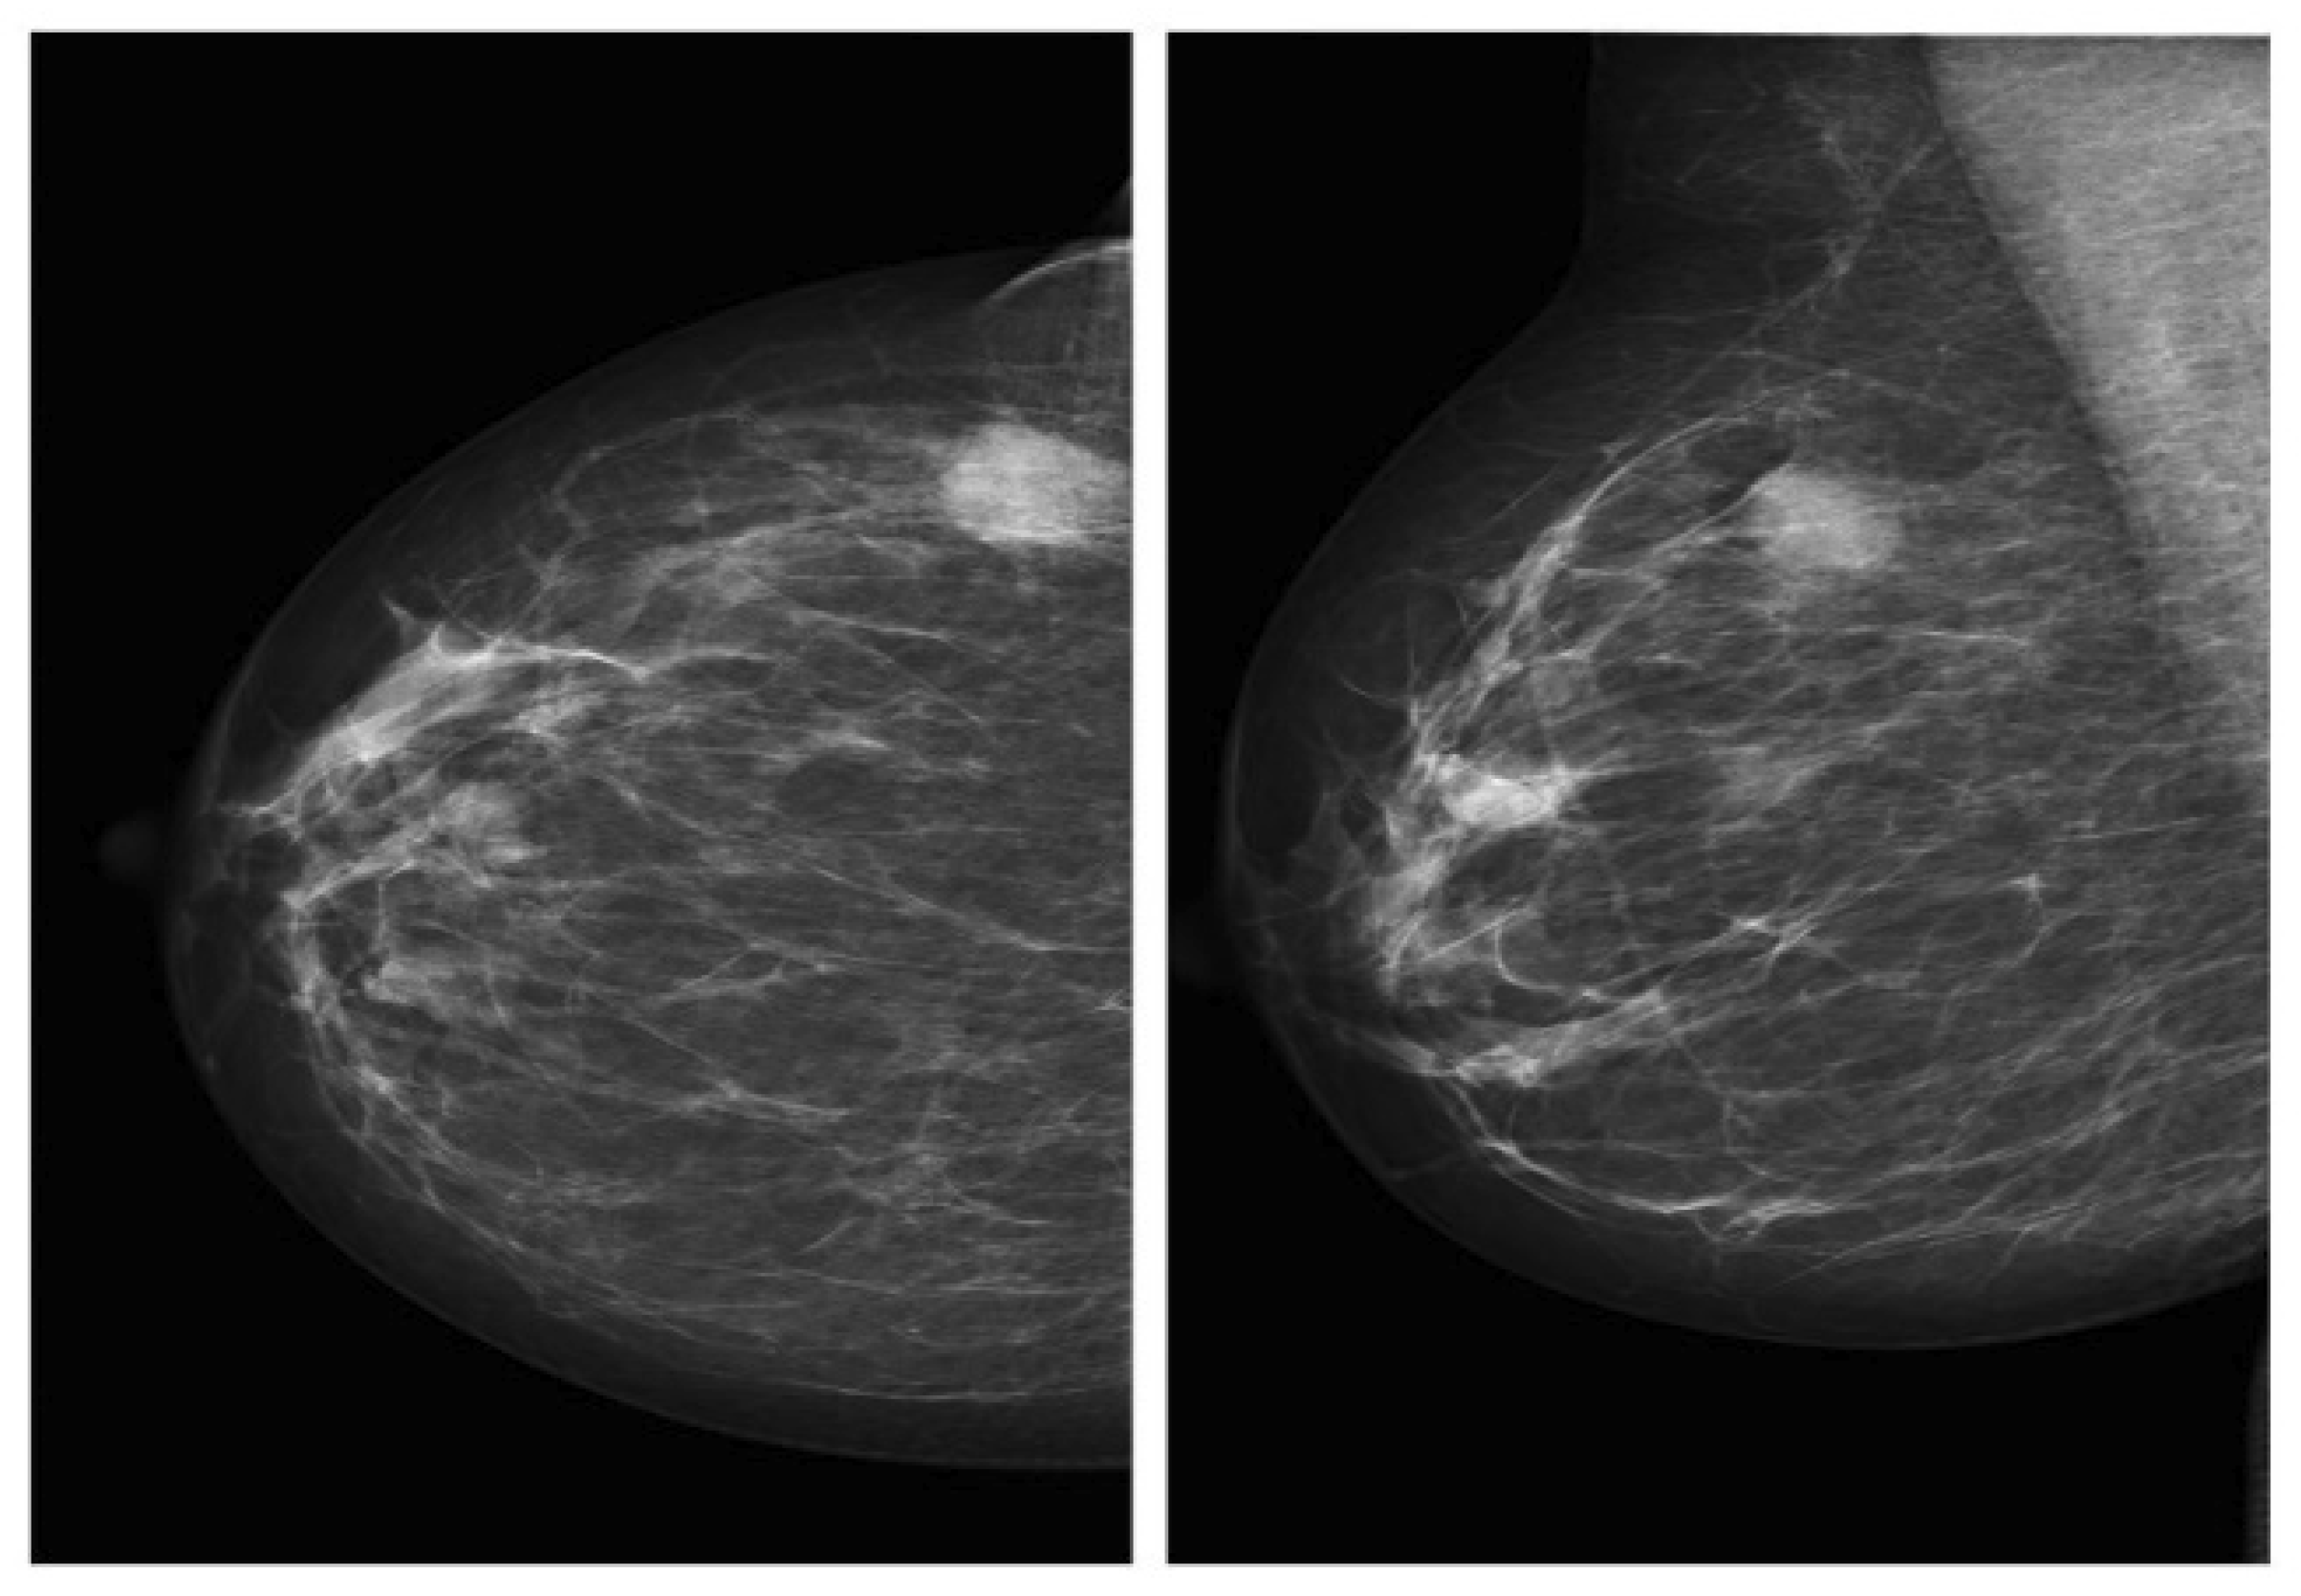

2.1.1. Mammography Datasets

| Dataset | Type | # of Images | View | Format | Classes | Resolution (Bit/Pixel) | Availability |

| DDSM [37] | Digital Mammogram (DM) | 10,480 | MLO/CC | LJPEG | Normal, benign and malignant | 8–16 | Publicly available |

| CIBS-DDSM [38] | Digital Mammogram (DM) | 10,239 | MLO/CC | DICOM | Benign and malignant | 10 | Publicly available |